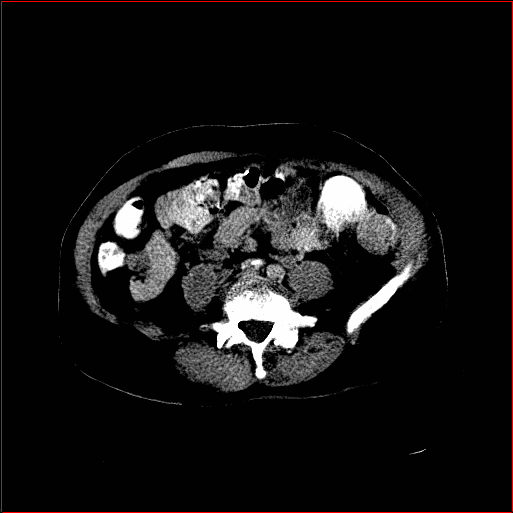

Abdomen Region

1×1×0.71\times 1\times 0.7

mm

512×512×768512\times 512\times 768

Refer to caption

Figure 4: MAISI-v2 segmentation-guided results for small to large volume size and three different regions.